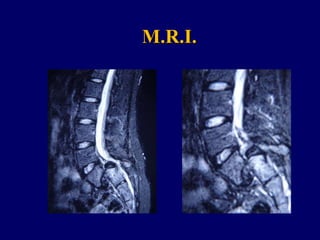

Mar. A.

Related to Isthmic Spondylolisthesis 4th – 5th degree

M.R.I.